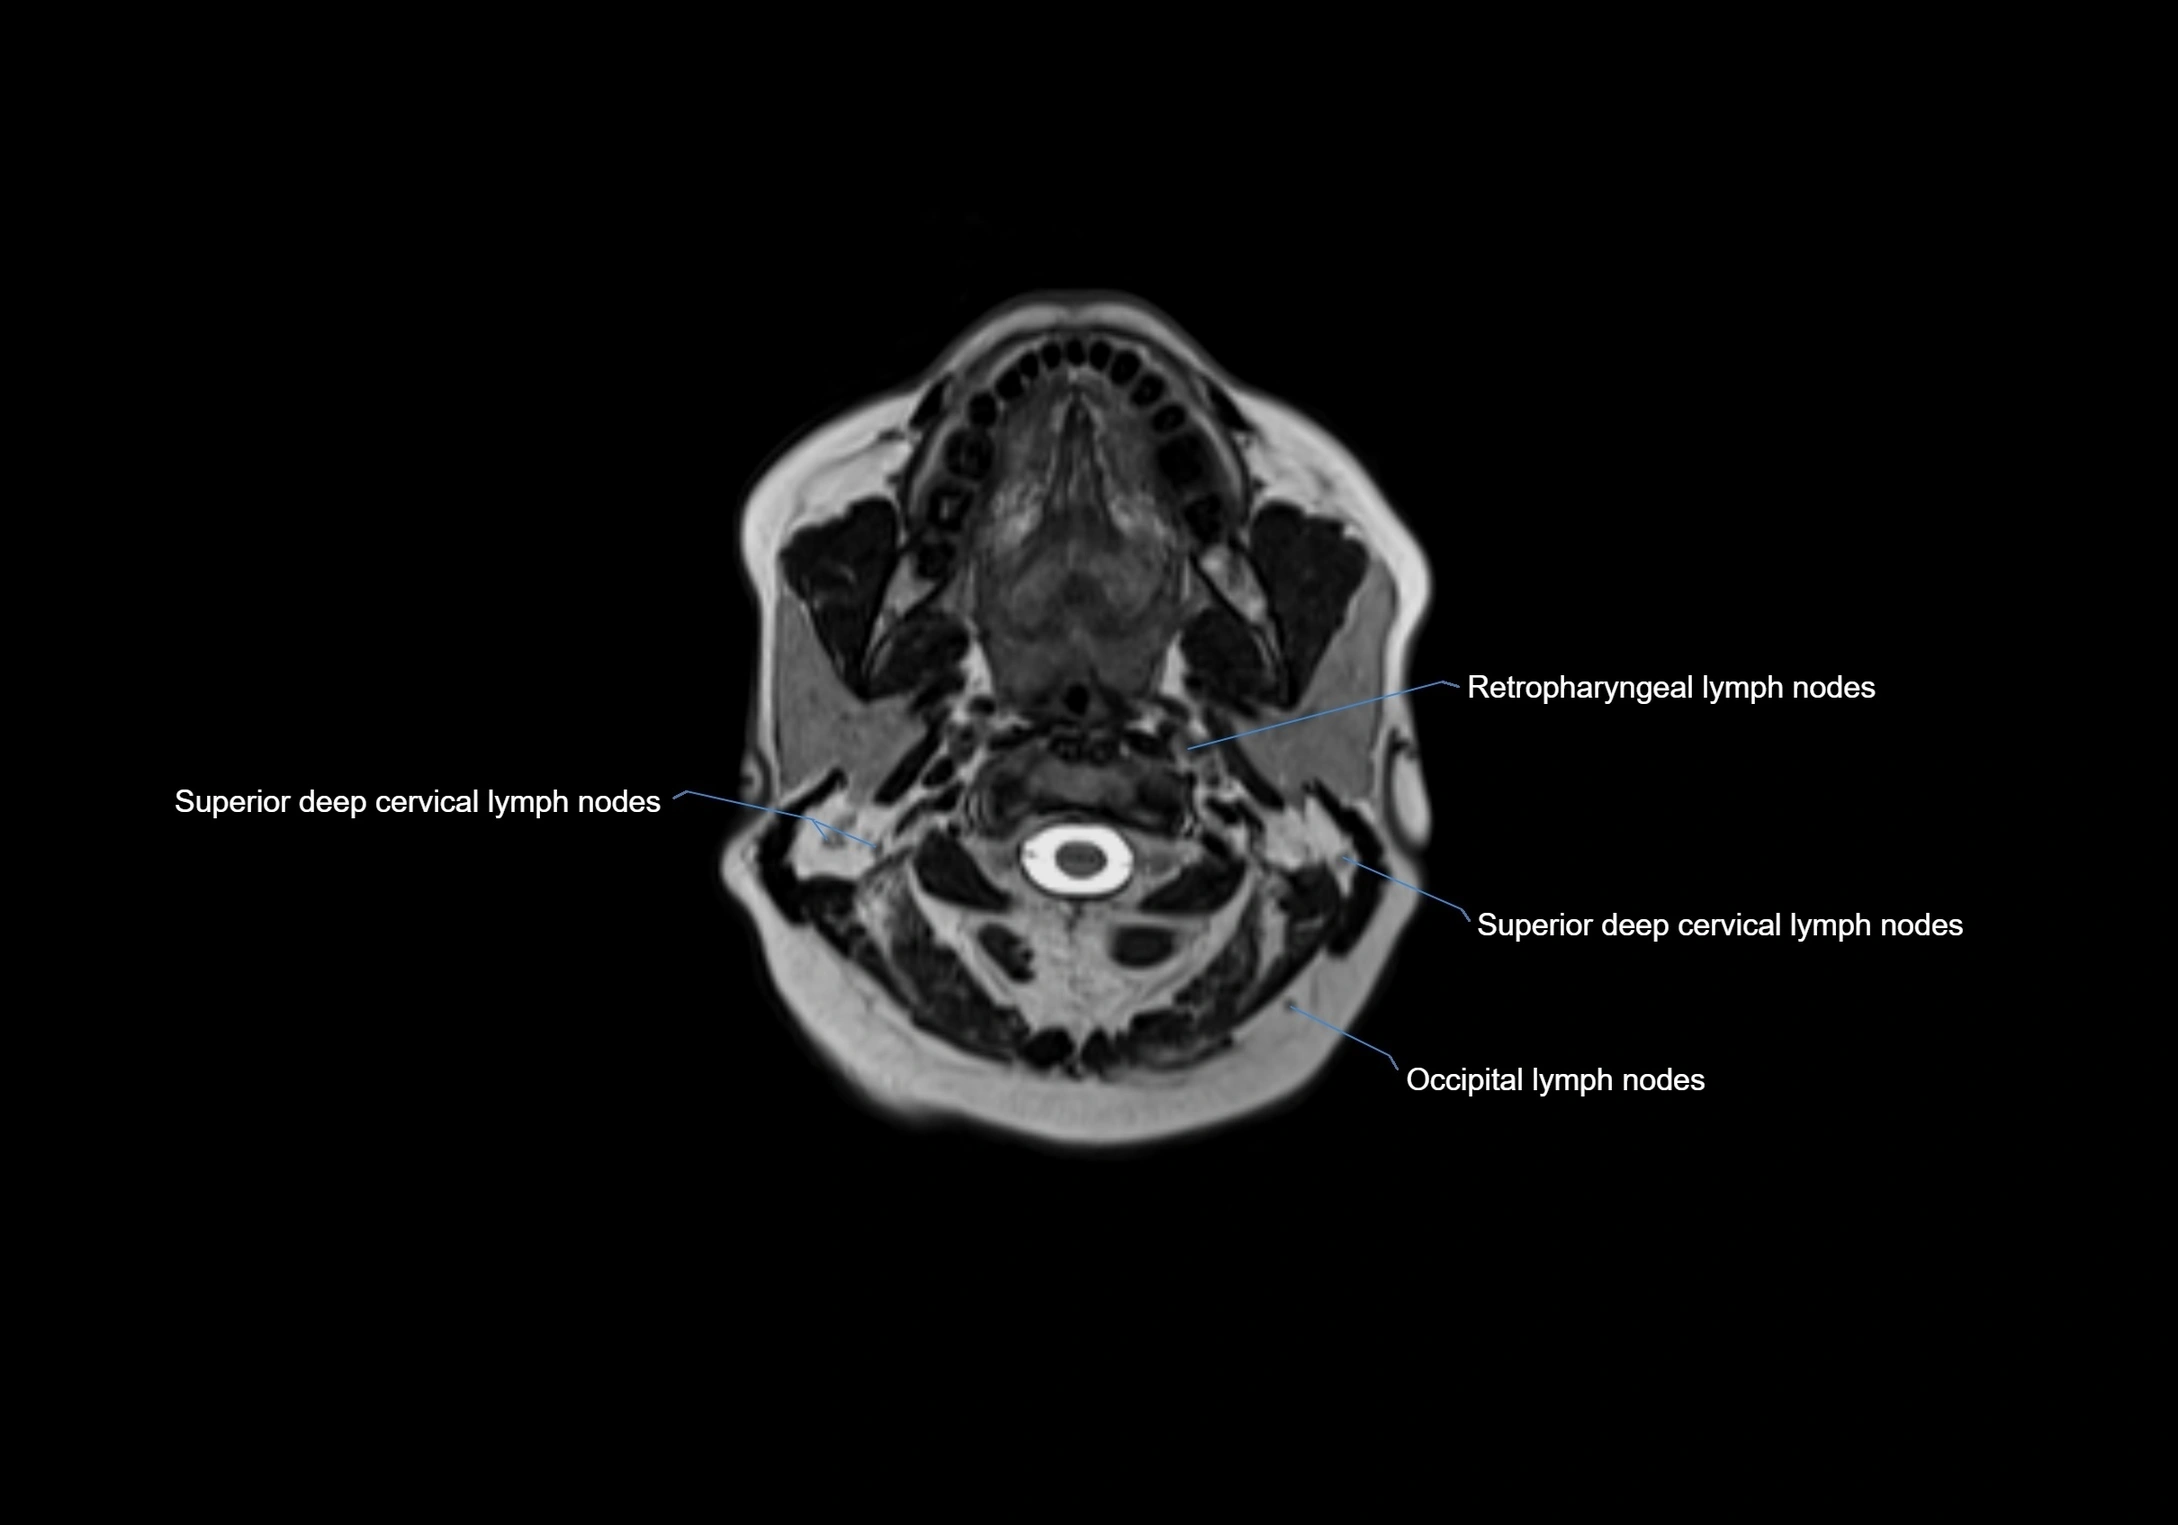

Accessory lymph nodes are small, secondary lymph nodes located along the main facial and cervical lymphatic chains, often adjacent to primary lymph nodes, such as preauricular, submandibular, or occipital nodes. They are typically less than 5 mm in diameter, embedded within subcutaneous fat or connective tissue, and may be variable in number and location. These nodes provide additional filtration and immune surveillance for lymph collected from the face, scalp, and neck regions. Accessory lymph nodes are usually non-palpable in healthy individuals but may enlarge in response to infection, inflammation, or metastasis, making them clinically significant.

Location

• Found along primary lymph node chains, including preauricular, submandibular, parotid, and occipital regions

• Embedded in subcutaneous fat or superficial fascia, often lateral or posterior to primary nodes

• Variable in number; may occur unilaterally or bilaterally, depending on individual anatomy

MRI images

image